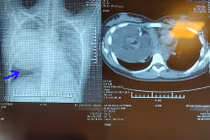

Các bác sĩ bệnh viện Ung bướu Hà Nội vừa phẫu thuật lấy khối u quái khổng lồ trong lồng ngực cô gái 19 tuổi. Khối u to, đè đẩy tim, chèn ép làm xẹp phổi, dính nhiều cơ quan nội tạng xung quanh.

(khoahocdoisong.vn) - U trung thất bắt nguồn từ những mô của nhiều lá thai, nằm lạc chỗ, phát triển chậm. Khi khối u khá to sẽ gây hiện tượng chèn ép hoặc thoái hóa ác tính.

(khoahocdoisong.vn) - Trung thất được phân chia làm 3 phần: Trung thất trước, trung thất giữa và trung thất sau. Các cơ quan của trung thất có các biểu hiện bệnh tật riêng.